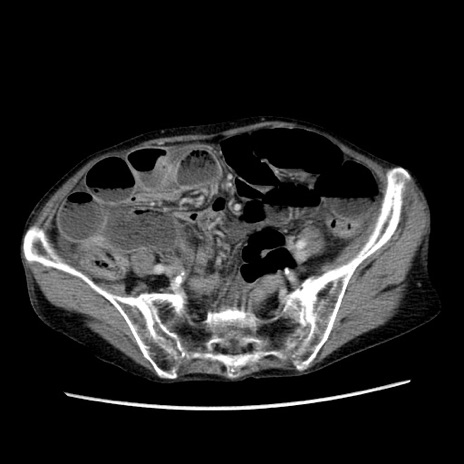

症例25(横断像)

【症例】80歳代女性

【主訴】胸のつかえ感

【現病歴】約9時間前に食後から胸のつかえた感じあり、嘔吐あり、来院。

【既往歴】胃癌(全摘)、胆摘、虫垂炎

【身体所見】心窩部に圧痛あり、反跳痛なし。

【データ】WBC 5700、CRP 0.05